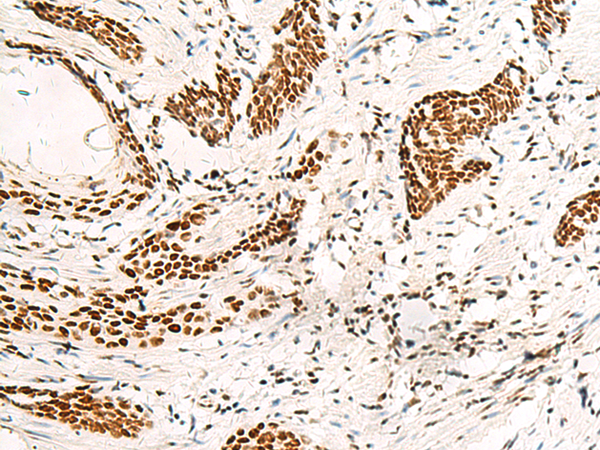

分类: 科研抗体货号: P13583别名: HNF6; HNF-6; HNF6A应用: WB,IHC反应种属: Human, Mouse, Rat